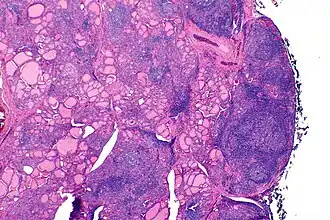

| Tiroide de indivíduo com tiroidite de Hashimoto observada em microscópio de baixa ampliação | |